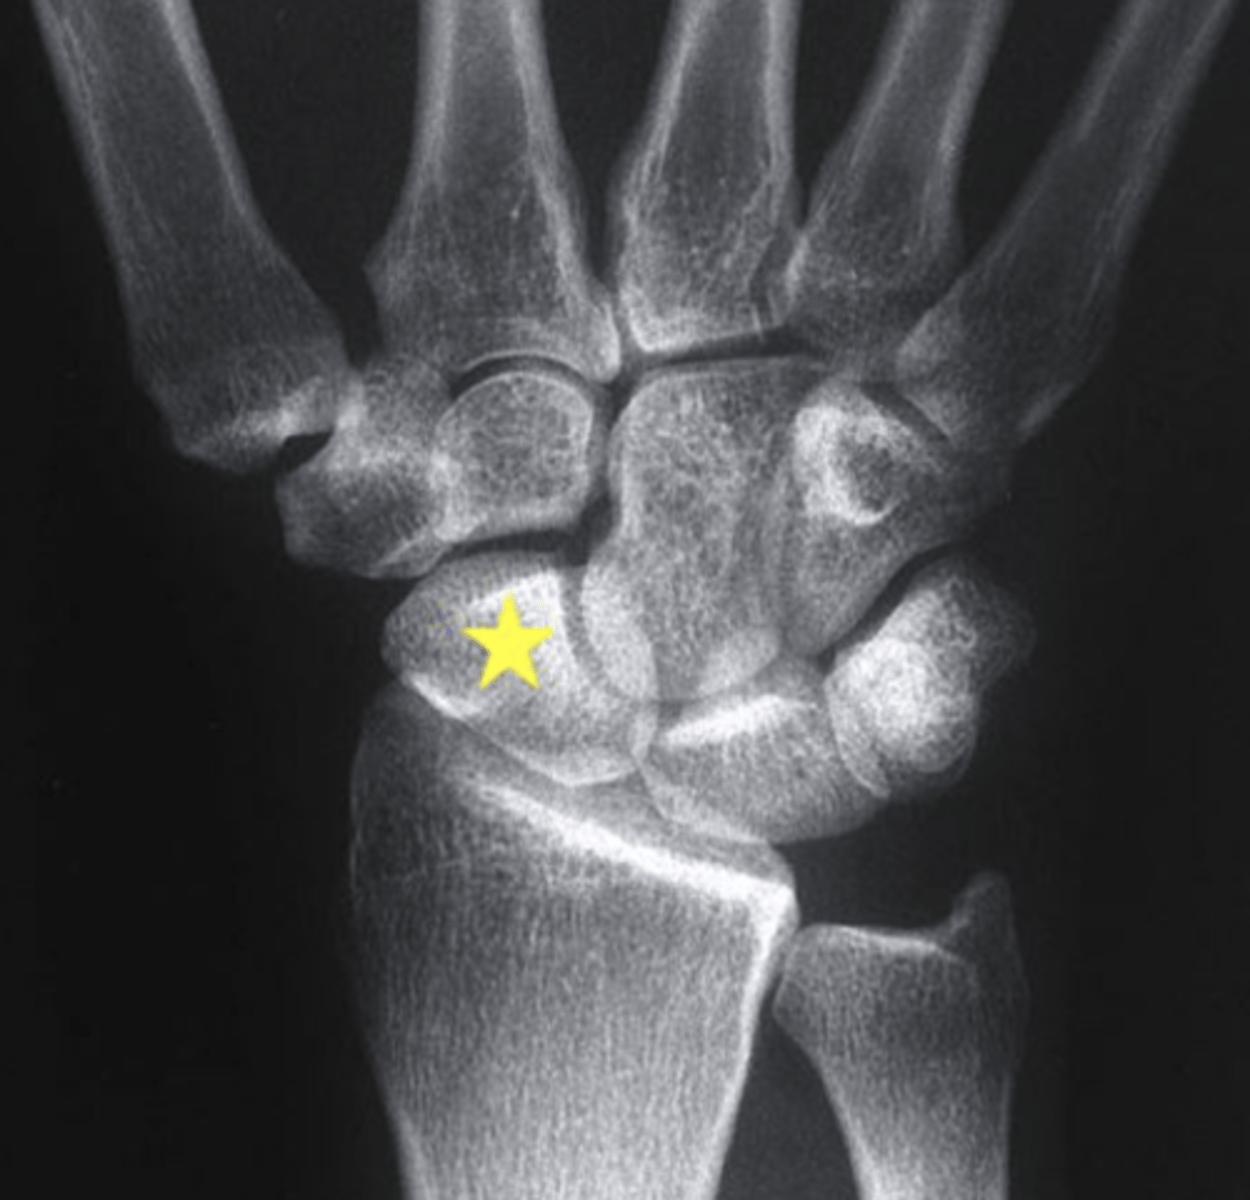

Which structure is highlighted by the star?

scaphoid